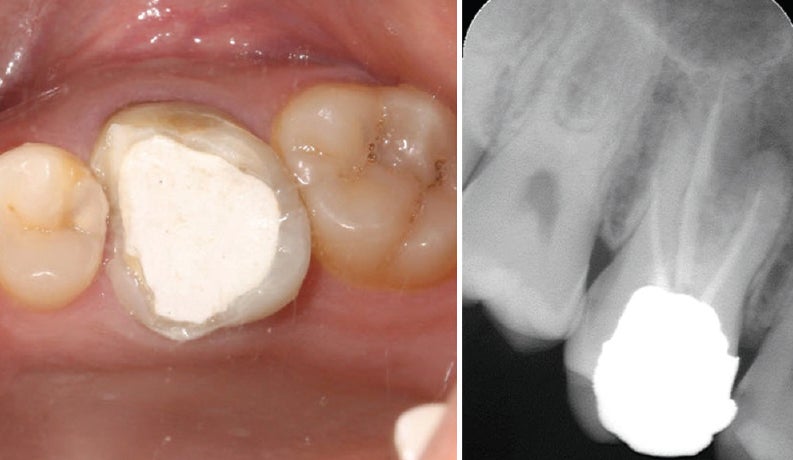

치아 크라운은 신경치료 후 약해진 치아를 보호하기 위한 보철물이지만, 시간이 지나면서 씹는 압력이나 이갈이, 단단한 음식물 섭취 등으로 깨지거나 금이 갈 수 있습니다. 특히 오래된 크라운은 더 취약하며, 방치하면 치아와 잇몸에 2차 손상이 발생할수 있으므로 빠르게 대응해야 합니다.

씹을 때 통증, 푹 꺼지는 느낌 등이 느껴진다면 크라운 손상 가능성을 의심해야 합니다. 특히 신경치료한 치아가 노출되었다면 즉시 치과를 방문해야 합니다.

- X‑ray 및 육안 진단 → 상태 확인

- 재접착 가능 시 임시/영구 접착 → 안 되면 새 크라운 제작

- 임시 크라운 장착 후 최종 크라운 장착 (1~2주 소요)